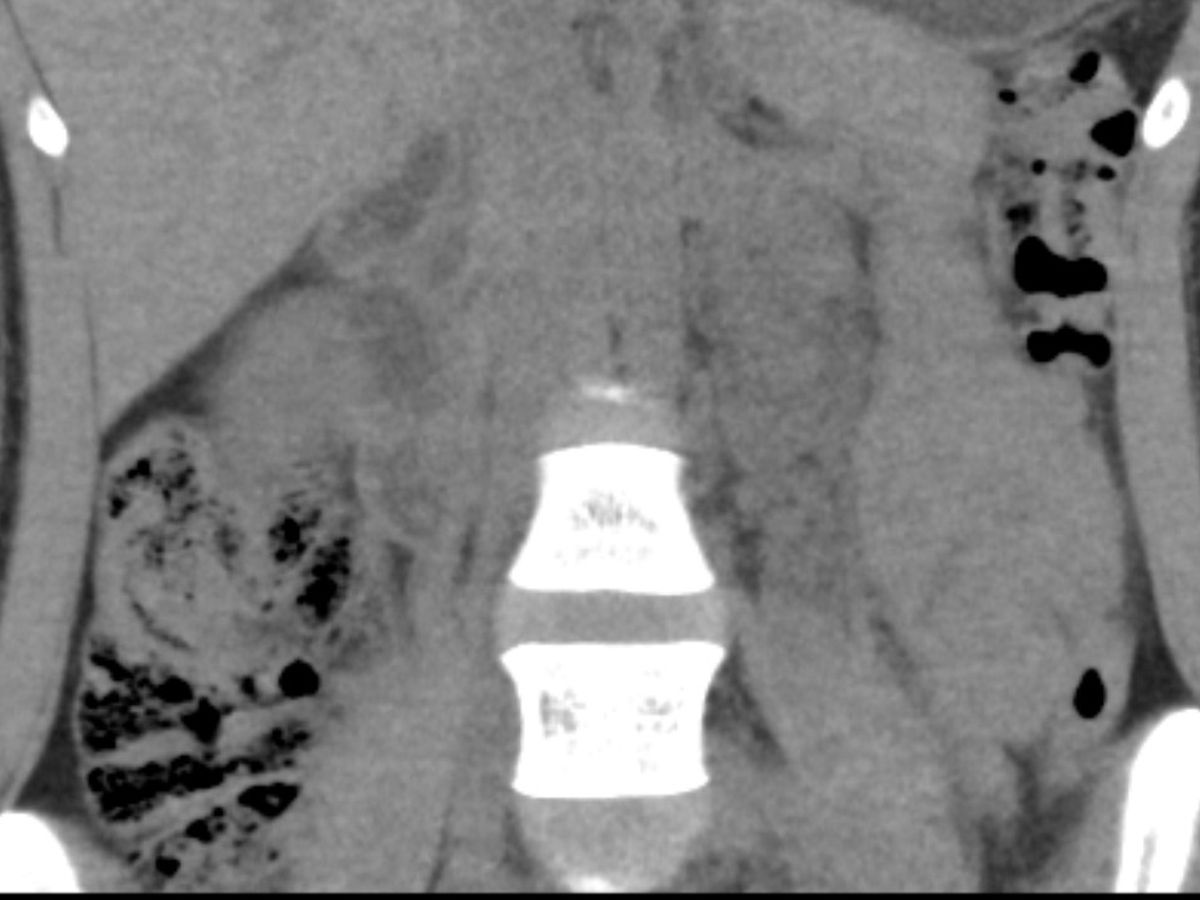

Aloha to all my friends & family. This has been something I have been trying to avoid for a long time; as most people know, I’m not one to ask for help unless there’s no other option. I have been diagnosed with a neurogenic tumor the size of a grapefruit, in my abdomen that has been taking a detrimental toll on my body and health. My tumor was discovered on Memorial Day weekend after multiple trips to the emergency room. Since then, I have gone through multiple rounds of testing and biopsies to diagnose the issue. We are still on the path of diagnosis as there are many different types of neurogenic tumors, but I have faith that we will find all the answers. I will be getting exploratory surgery on December 6th followed by chemotherapy and multiple de-bulking surgeries in the near future. My surgeon and procedures are all in San Francisco, which has required my parents & partner to miss out on work to help me with travel. I am hoping to help relieve the financial strain on us all through this time. I was raised by the strongest family imaginable, I know all will be well in due time. I also want to thank all my aunties, uncles, and cousins that have been so supportive since the beginning. Truly so blessed to be surrounded by so much love and I am so grateful for it all!